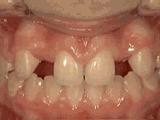

第四种:

牙列拥挤,牙槽骨过窄,牙齿没有足够空间,只好前后左右高低上下乱长,经过矫正后的牙齿是这样的~